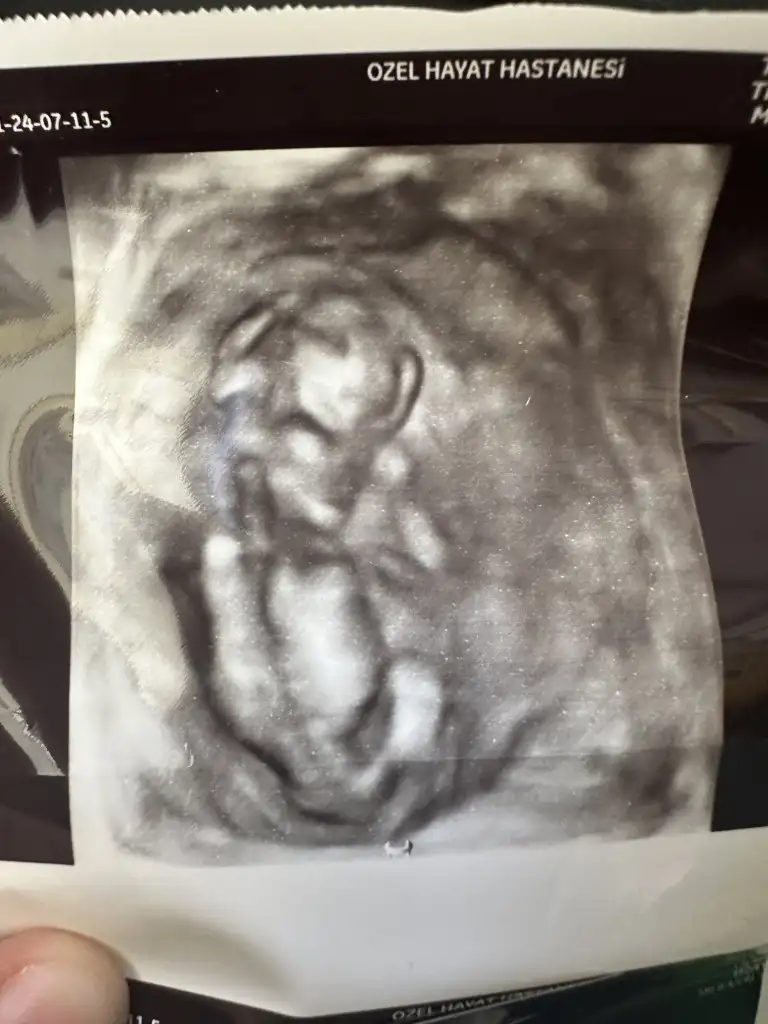

Ultrason görüntüsü de 17 Mart tarihine ait. Yani döngümün 21. günü. Belki USG ultrason görüntüsünden anlayan birileri çıkar :(

Eki Görüntüle 3569359